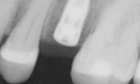

Before and After Pictures

The above images demonstrate the sequence of events for replacing a single missing tooth with a dental implant. The implant fixture is placed and allowed to heal, then a post or abutment is seated, and then a final crown is placed on top.